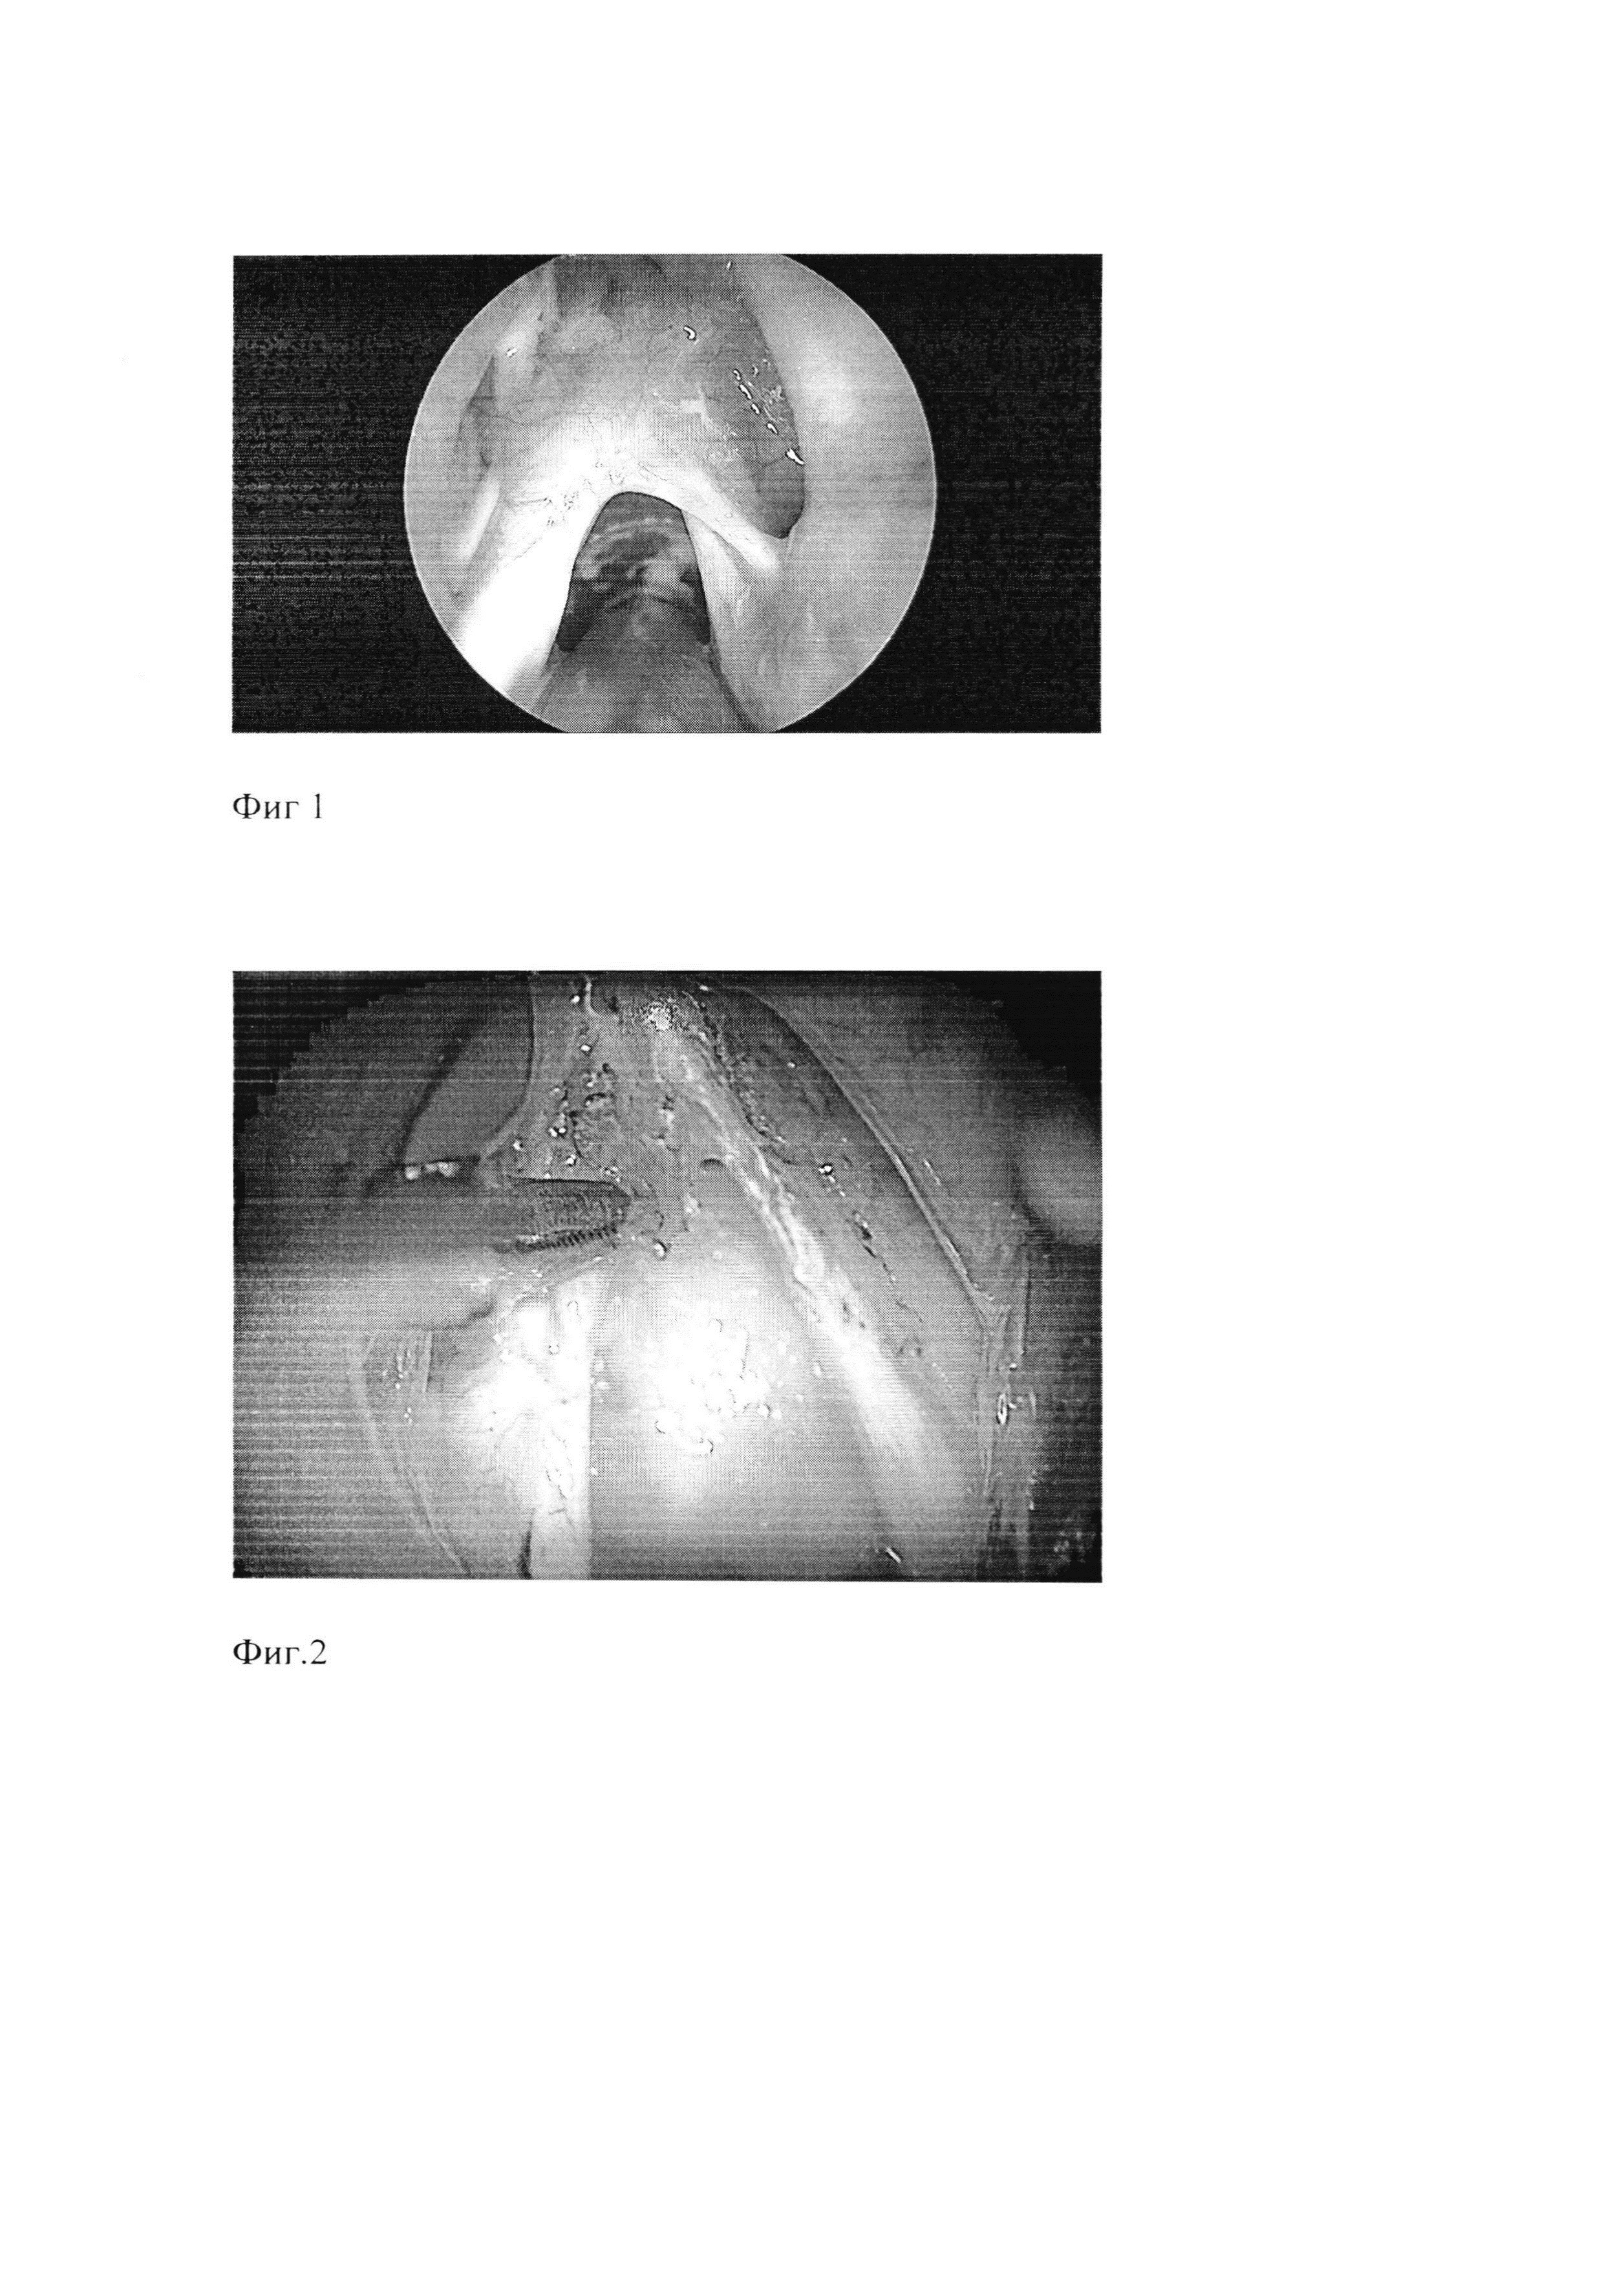

Фиг. 1. Фото рубцовый стеноз среднего отдела гортани

Фиг. 7. Эндоскопическая картина гортани через 1 месяц.

Эндоскопический осмотр проводился в первые 5 дней после операции и через месяц, при этом восстановление голоса отмечалось к вечеру после операции, отек и фибрин с послеоперационной раны сошел на 3 сутки после операции, при осмотре через месяц - признаков рестеноза гортани нет, голос звучный.

Эндоскопический осмотр проводился в первые 5 дней после операции и через месяц, при этом отек с послеоперационной раны сошел на 2 сутки после операции, фибрин - на 4 сутки после операции, при осмотре через месяц - просвет гортани сохранен, признаков рестеноза гортани нет, голос звучный. При закрытой трахеостоме дыхание удовлетворительное. Выполнено ушивание трахеостомы.